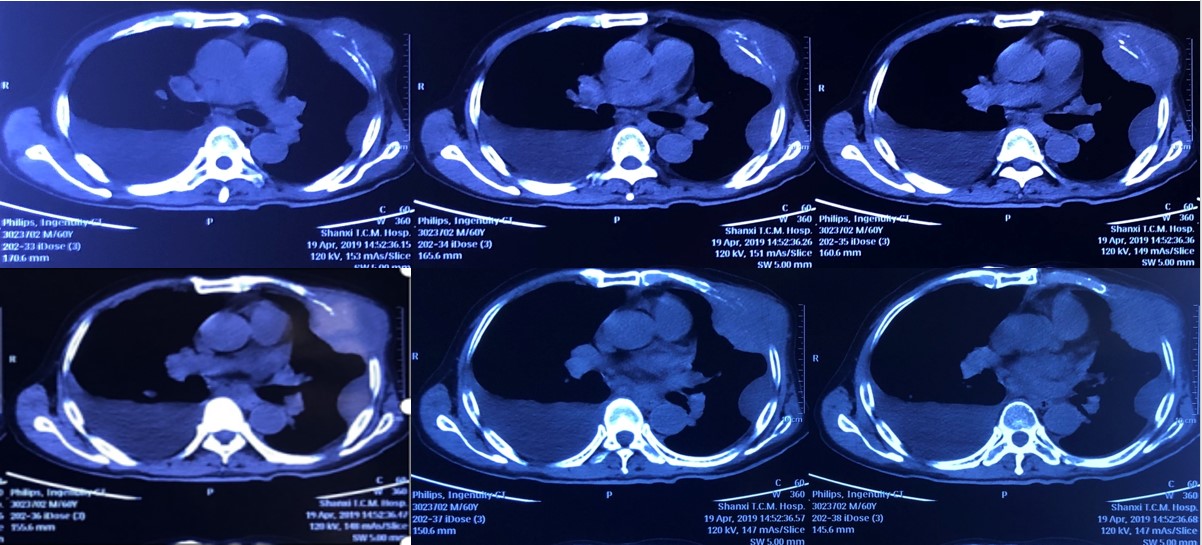

2019年5月29日使用信迪利单抗3周期后复查CT,显示肋骨及胸膜处的病灶进一步缩小(图3)。

图3. 2019年5月29日使用信迪利单抗3周期后CT复查结果

在经过3个周期PD-1治疗后,患者病灶明显缩小,疼痛、咳嗽咳痰症状消失,食欲正常,精神状态明显改善。